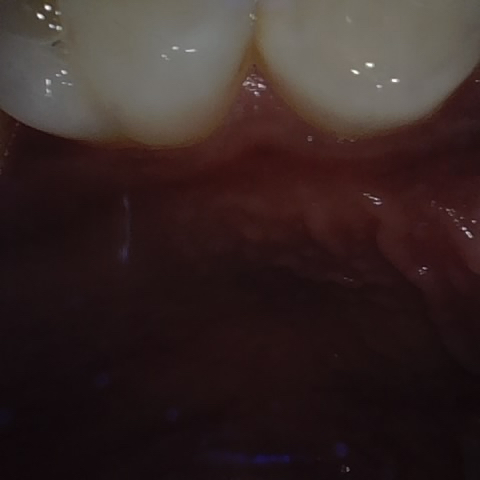

Annotated as "Good"